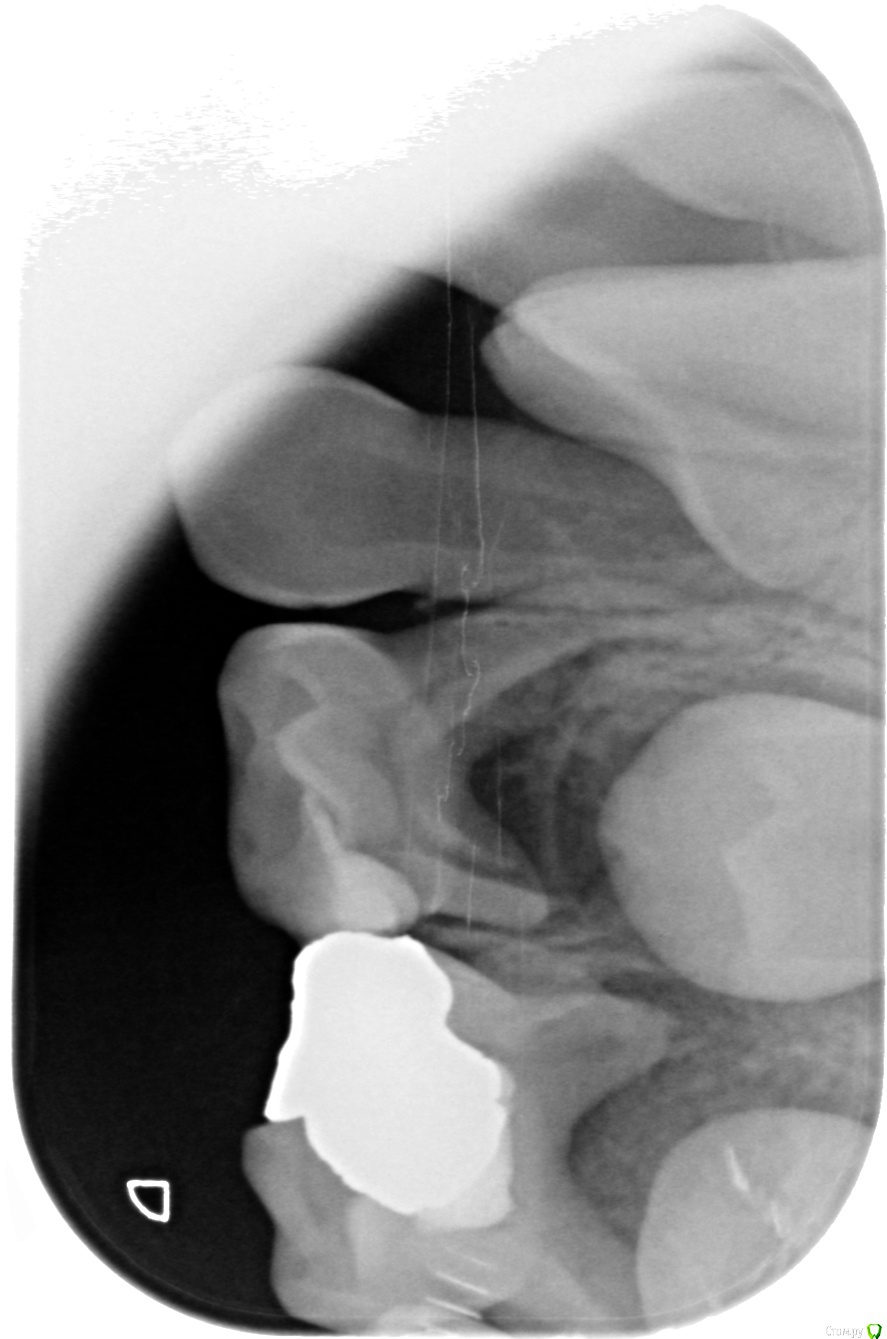

alezz Опубликовано 4 февраля, 2019 Поделиться Опубликовано 4 февраля, 2019 Вчера у ребенка разболелась десна и немного припухла щека. Сегодня были в клинике, врач после осмотра и рентгена сделала вывод что из-за неправильного пломбирования инфекция заразила нервы в трех молочных зубах и из них пошла в десну. Все зубы боковые, молары. Два рядом справа и один слева. Она мне показала рентгеновкие снимки, там действительно видно что корни у этих зубов сильно разрушились в сравнении с другими.Я предложил их просто вырвать. Но она сказала что ребенку еще только 7.5 лет, а постоянные зубы на этих позициях вырастают в 11 лет. Если их удалить, то другие молочные зубы сместятся и коренные потом неправильно вырастут. Она предлагает удалить пломбы, попробовать пролечить каналы и с новыми пломбами сохранить эти зубы хотя бы еще на год. Мне в этом во-первых не нравится то, что инфицированные зубы будут постоянным источником инфекции во рту. Она сама сказала, что полностью вылечить их уже не получится. И во-вторых просто не хочется платить за сложное лечение молочных зубов.Действительно ли настолько важно в 7,5 лет бороться за сохранение молочных зубов? Ссылка на комментарий

alezz Опубликовано 5 февраля, 2019 Автор Поделиться Опубликовано 5 февраля, 2019 Снимки Ссылка на комментарий

Дмитрий Л. Опубликовано 5 февраля, 2019 Поделиться Опубликовано 5 февраля, 2019 4е моляры молочные удалить, 5й можно попробовать отстрочить ненадолго Ссылка на комментарий